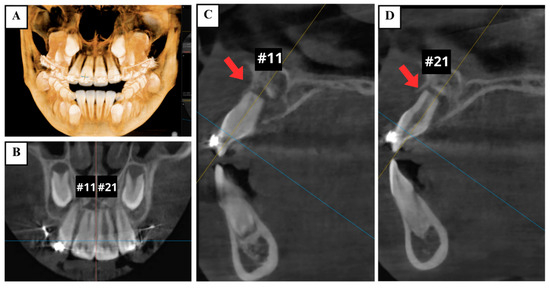

2.2. Preoperative Examination

2.3. Diagnosis

2.4. Treatment Plan